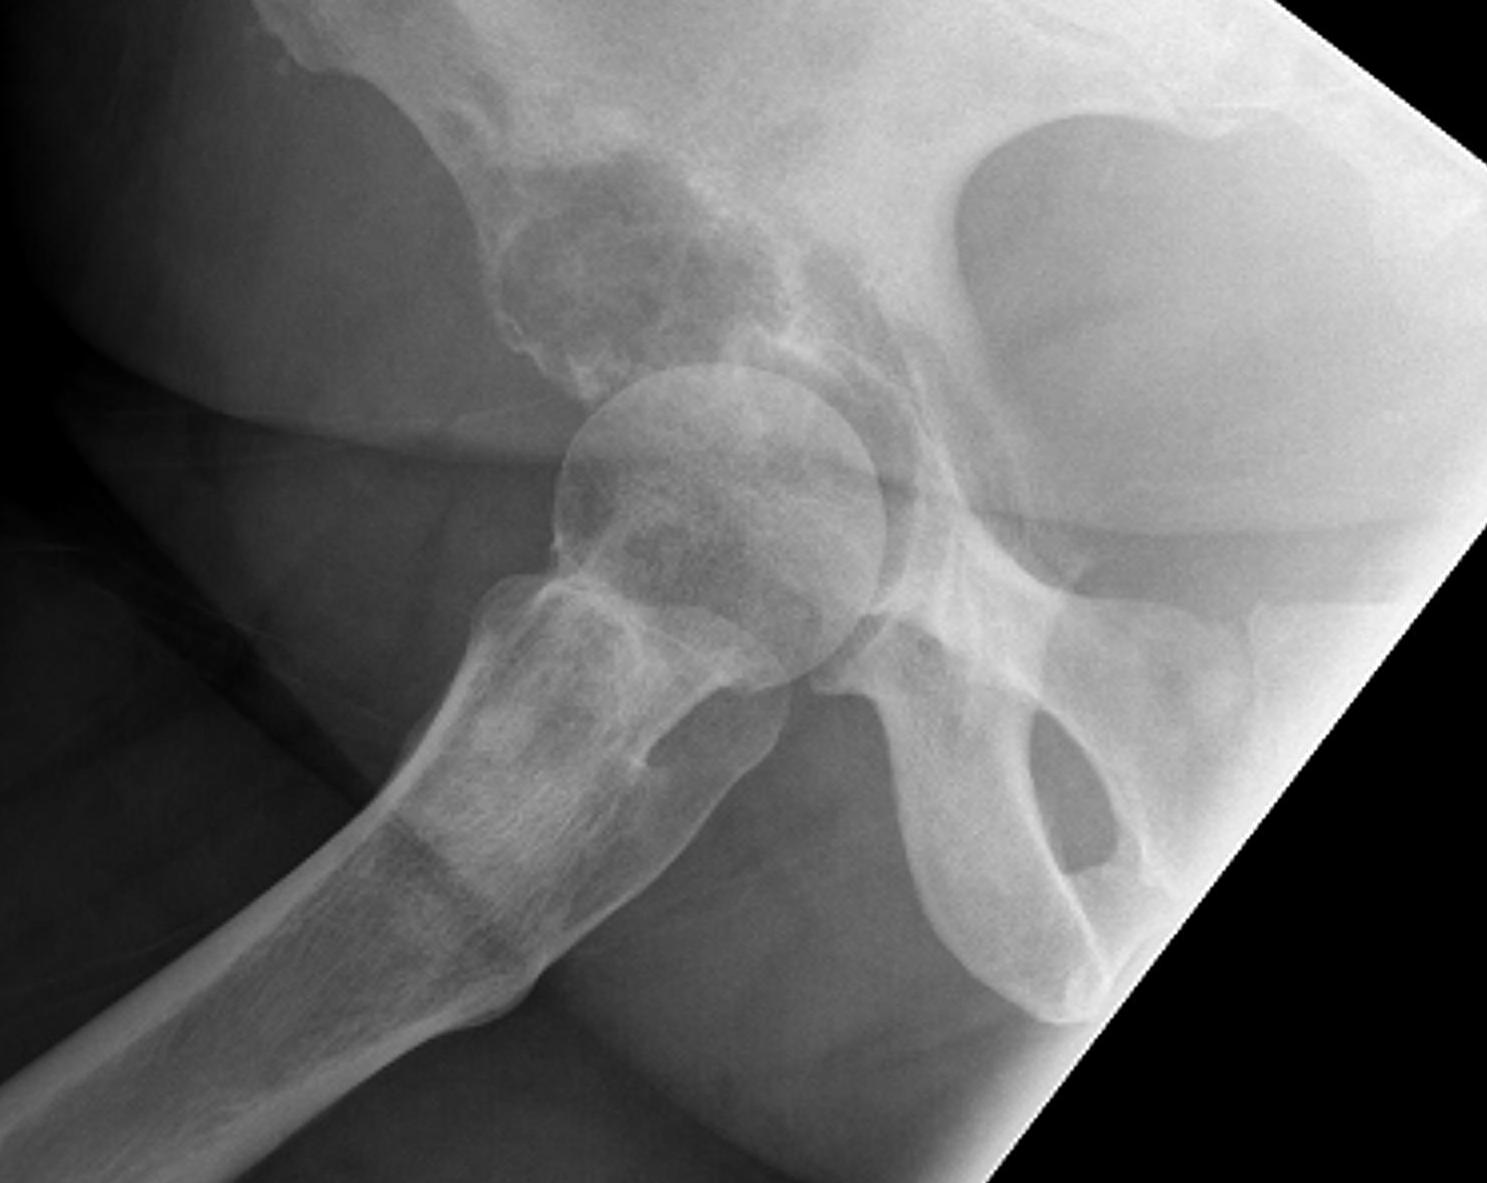

Femoral Neck pathological fracture / Major bone loss

Issues

- fracture unlikely to heal

- hemi versus THA

- long versus short stems

Hemi v THA

Consider life expectancy of patient

Femoral stem length

- 203 patients with proximal femoral metastasis treated with arthroplasty

- no increased revision rate with short stems

- increased complications with long stems, especially cardiopulmonary complications

Femoral neck stabilization

- sufficient bone for fixation?

- determine if lesions further down femur (xray entire femur)

- consider augmentation with PMMA / cement

Plate versus IM nail

Meynard et al Orthop Traumatol Surg Res 2020

- 309 cases proximal femoral metastasis

- plate versus IMN versus arthroplasty

- no difference in functional outcome

- increased complications with plating